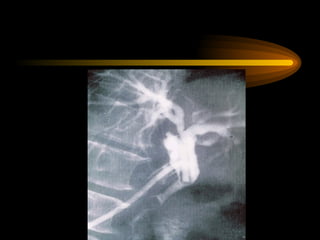

TM bình thường

Soi tm